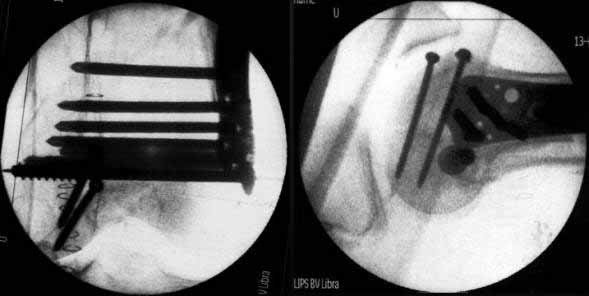

On Thursday afternoon he was alright, he is a very active man and he was moving well both knees. Later that evening he told me that while he was a little bit asleep he turned on the bed and felt pain and that the femur was loose. Here are the X-rays we took.

In this case, the fixation might have failed because of inadequate purchase of the side plate to the shaft. I say this because the initial lateral xray shows that the plate seems to be fairly anterior to the mid-axis of the femoral shaft.

Once the plate pulled off of the shaft, it continued to pull out of the distal segment. With the short unicortical screws used for shaft fixation, it is imperative that the plate be applied precisely at the midline (widest diameter) of the femur. If it is applied even slightly anterior or posterior to the midline, the screws just don t engage the cortex. You can t tell by feel, since the screws lock firmly into the plate. The only guidance that imaging provides is to visualize the plate centered exactly on the bone on a good lateral projection, which is difficult to obtain intra-operatively. I have resorted to making a 3-4 cm incision at the top of the plate so that I can verify that the plate is exactly centered over the femur at its proximal tip.

A second pearl is to place at least one or 2 lag screws between the condyles for intrafragmentary fixation before applying the LISS. Although screws were used across the coronal plane (Hoffa) fracture, I do not see any lag screws from lateral to medial. The LISS screws are designed to maintain the reduction of the distal femoral condylar mass to the shaft, but they do not function as lag screws. The intra-articular portion of the fracture demands open reduction and rigid internal fixation according to established principles; the LISS is used to then stabilize the reconstructed distal femur to the shaft.

I was taught not to put the plate in the middle of the shaft in a true lateral view of the femur, but rather slight anterior and internally rotated so the end part will adapt to the trapezoid shape of condyles, but still the screws will be in the maximum diameter of the shaft. On the post-op X-ray you can see a true lateral view of the femur (the posterior part of the condyles are aligned);but not of the plate (you can see them coming under). I can assure you that the plate was completely centered on the shaft.

On intraoperative fluoroscopy with external rotation of the thigh we confirmed that the plate was completely centered in that case.

Lateral x-ray does not adequately show proximal shaft & plate alignment with it. Do you think the plate was too anterior? This is an acknowledged mode of failure, as tangential unicortical screws may have minimal purchase, in spite of drill-tip passing through hard bone, and of course good torque as screw is tightened (into plate). If not easy to confirm intra-operatively, a short proximal incision can help to ensure correct alignment of plate with shaft.

Condyles have separated. Would separate (peripheral ? 3.5mm, lag screws, medial to lateral or lateral to medial outside LISS footprint) lag screws have been helpful? Intercondylar fracture needs open reduction and good interfragmentary compression.

LISS is a bit proximal, and screws are not parallel with joint line. Is there excessive valgus on appropriate AP views? You might want to check the mechanical axis using electrocautery cord stretched across knee, from center of femoral head to middle of talus.